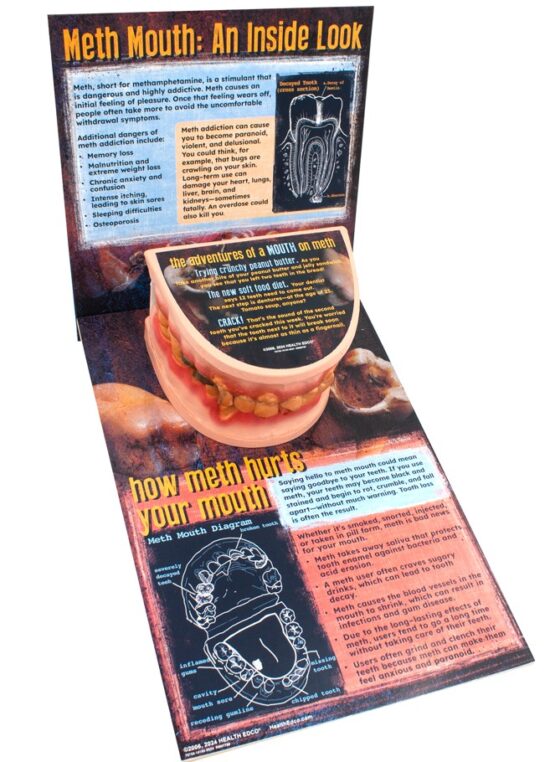

Graphically depicting the grisly effects of methamphetamine on the mouth, this giant mouth display is ideal for schools, law enforcement agencies, and other organizations looking to give teens and young adults compelling reasons to stay away from meth.

The 3-D, handpainted mouth model shows the oral consequences of meth use, such as missing teeth, severely decayed teeth, broken teeth, receding gums, and more. Also includes a tongue model with an ulcer.

Informative text explains how meth harms both the mouth and body and drives home the message that meth is a dangerous drug. 10″ x 10½” x 16½”.